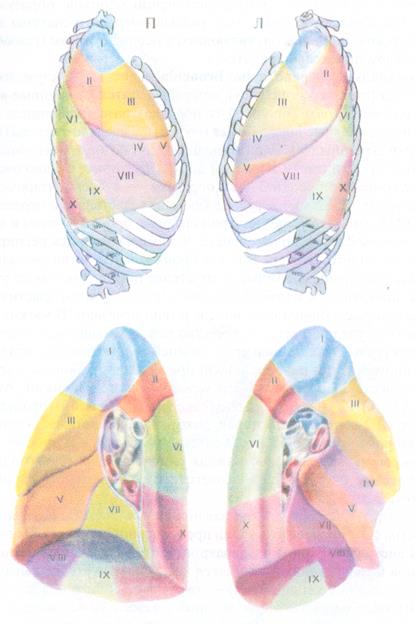

Анатомические изображения сегментов легких различных животных

Раздел: Другие животные